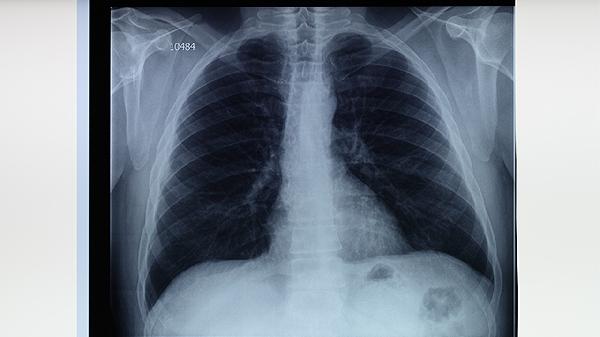

在服用抗结核药物期间,少量抽烟并不是一个好主意。虽然偶尔抽一根烟可能不会直接影响疾病的进展,但香烟中的有害物质,如尼古丁和焦油,会对肺部健康产生负面影响,特别是在肺结核治疗期间。吸烟可能会加重病情,延缓康复进程。为了更好地恢复健康,建议患者在治疗期间尽量避免吸烟。

香烟中含有多种有害物质,这些物质会对肺部造成损害。尤其是在肺结核的治疗过程中,肺部已经处于较为脆弱的状态,吸烟可能导致病情恶化或引发其他呼吸系统疾病。